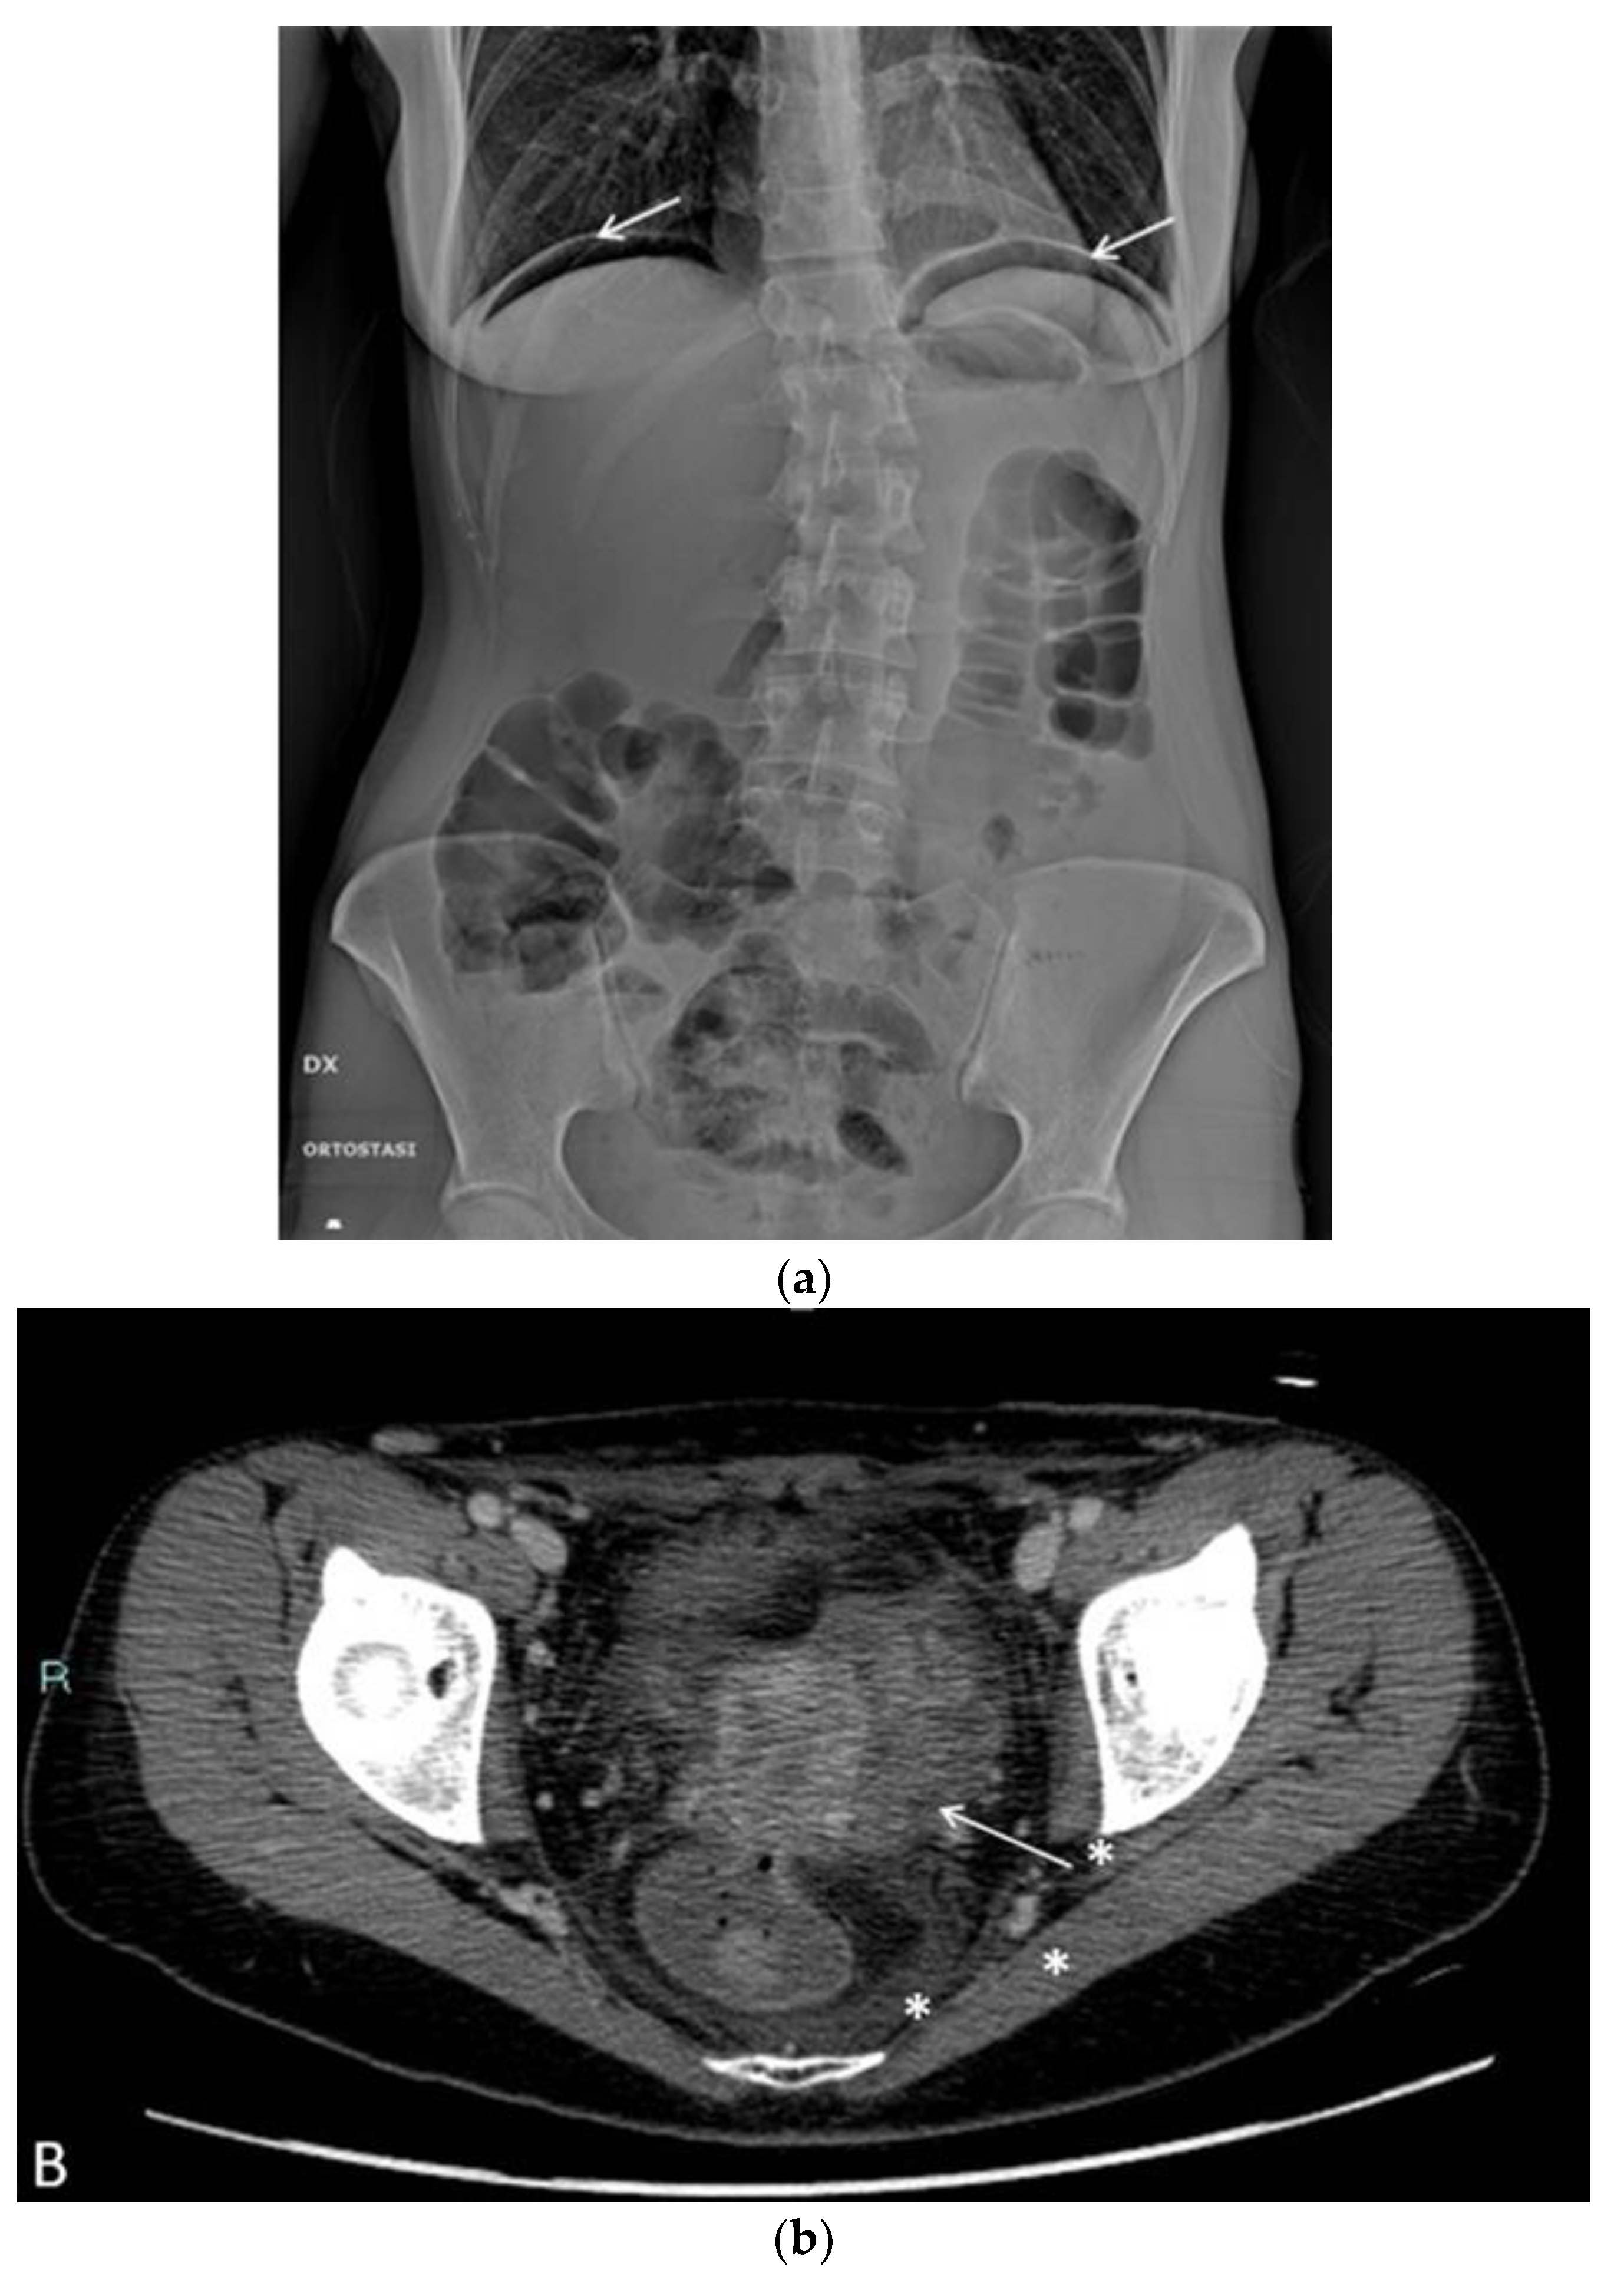

In the postoperative course, the patient experienced nonspecific symptoms: she remained afebrile, had mild pelvic pain at the site of the vaginal suture, which was managed with paracetamol as needed, and had diarrhea throughout the hospital stay. Only on the fifth postoperative day, malodorous secretions were observed in the vagina, and the patient was promptly examined for suspected vagino-rectal fistula. Immediate antibiotic therapy was initiated, and further diagnostic and radiologic tests confirmed the clinical suspicion of vagino-rectal fistula (Figure 6a–c), and the patient undergone adequate surgical treatment.

Figure 6. (a) Plain radiography shows free sub diaphragmatic air (white arrows). (b) Contrast enhanced CT. A small fistula (white arrow) connects the rectum with the upper portion of the vaginal canal. Diffuse thickening of soft tissues close to the mesorectal fascia is associated with a thin fluid layer (asterisks). (c) A frame of fluoroscopy obtained by single contrast enema performed with gastrografin. The contrast medium, injected transvaginally through a small tube (asterisk), spreads into the surrounding soft tissues (white arrows) and, to a lesser amount, into the rectum (arrowhead), confirming the presence of a pervious fistula.